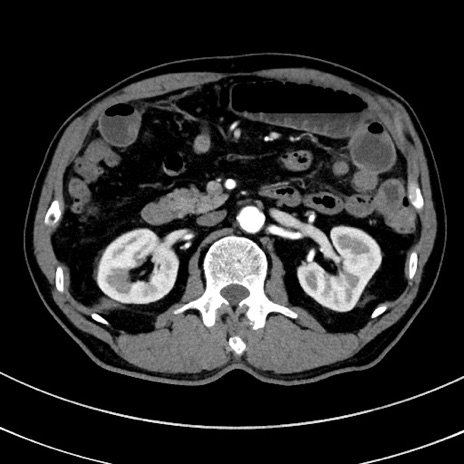

症例8(横断像)

【症例】 60歳代男性

【主訴】 黒色吐物

【現病歴】 4日前から嘔気自覚、2日前の朝食後にも嘔気あり、自分で手で嘔吐反射起こし嘔吐したところ血が混ざっていたため受診。

【既往歴】 5年前汎発性腹膜炎を伴う急性虫垂炎で手術、高血圧、前立腺肥大症、高脂血症

【身体所見】 腹部正中に手術癩痕あり 腹部平坦・軟圧痛なし膨満感あり

【データ】WBC 8400、CRP 4.54